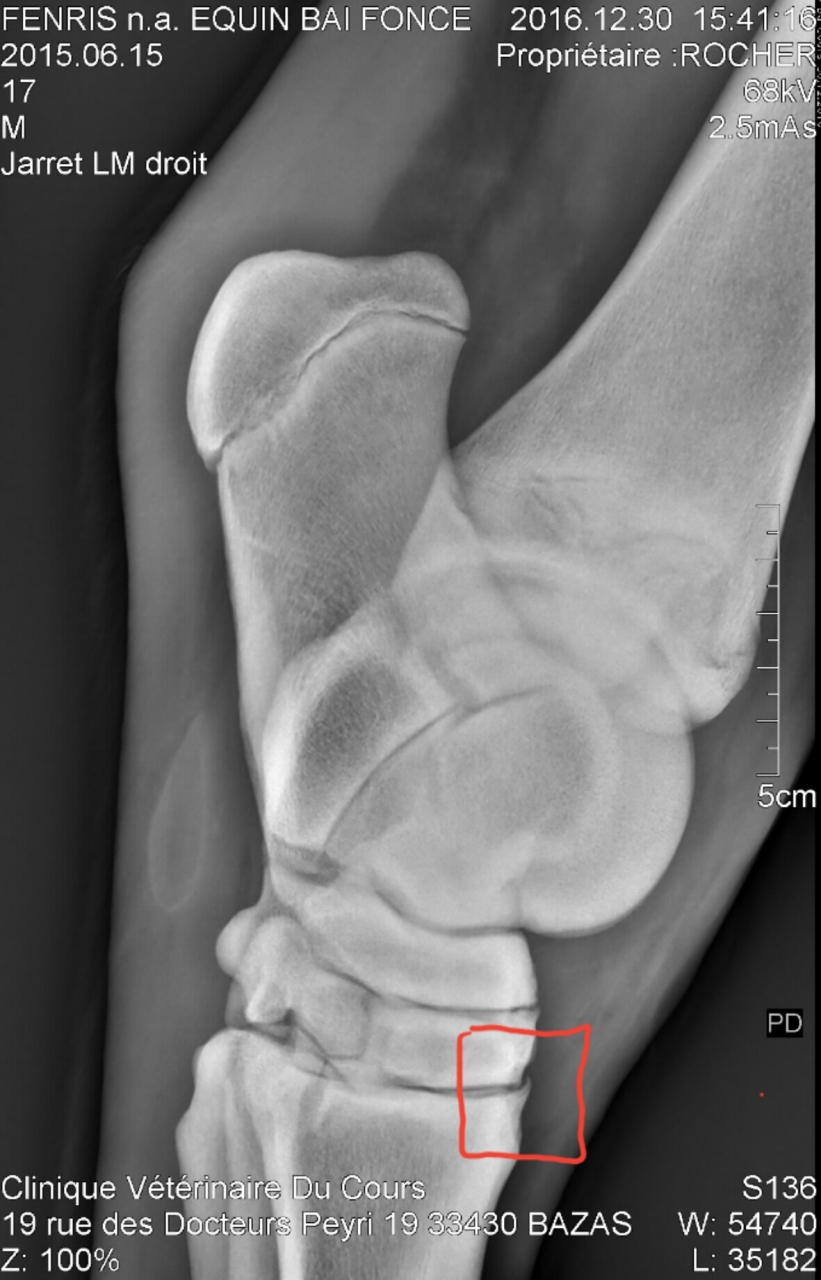

Par moncheval33 : le 31/12/16 à 17:54:20

| Dire merci | J'ai reçu pas mal de clichés, je vous en mets un pour le jarret droit et un pour le jarret gauche de toute façon c'est super dur à interpréter. Jarret D (ce que j'ai entouré en rouge est il me semble ce que la veto interprète comme de l'arthrose, cet sorte de bec) ![]() Jarret G (les flèches montrent ce qui serait de l'arthrose et le cercle situsitue l'endroit où est le fragment mais je ne le trouve plus précisément ... la veto m'a montré tellement de choses c'est difficile de tout mémoriser) ![]() |